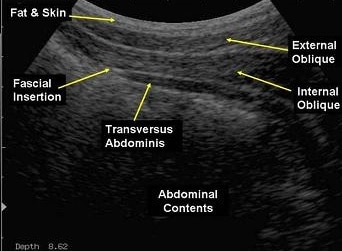

Real-Time Ultrasound for Assessment and Biofeedback Training

Real-time ultrasound (RTUS) revolutionises the assessment and treatment approach in pelvic health physiotherapy. This safe and non-invasive tool allows both you and your therapist to watch your abdominal and pelvic floor muscles work in real-time. This live visual feedback ensures you’re activating the right muscles optimally.